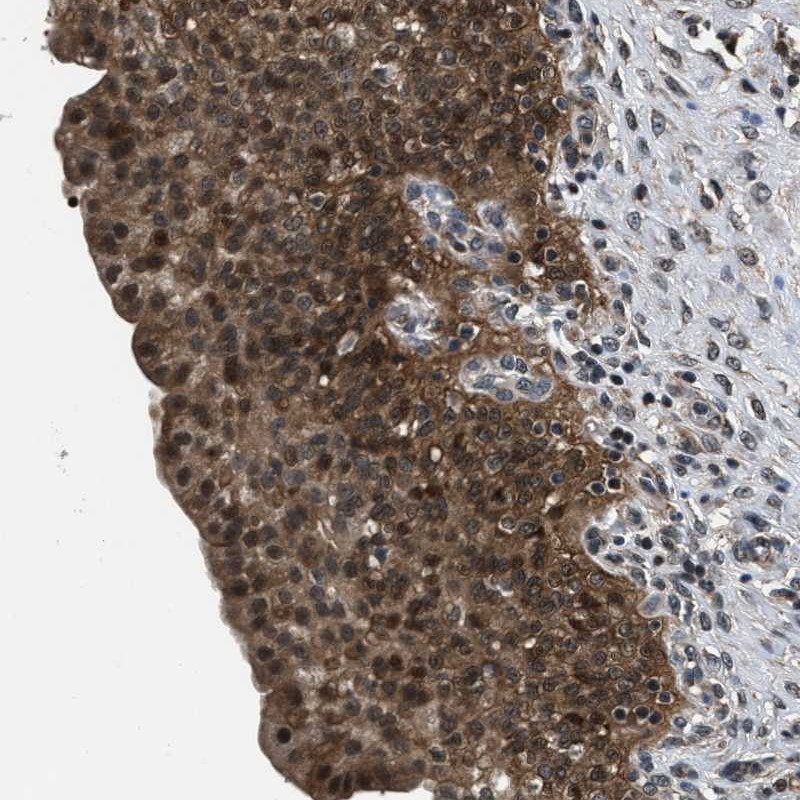

Immunohistochemical staining of human urinary bladder shows distinct cytoplasmic and nuclear positivity in urothelial cells.